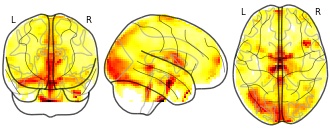

"name": "Multi_VBMsmaller_fMRIdecreased",

"description": "Multi-modal analysis in BPD. Brain regions exhibiting smaller gray matter and decreased activation during emotion processing in BPD compared to healthy controls. Note: Results were thresholded at p<.0025. Note2: Results were updated (see Erratum for this publication).",